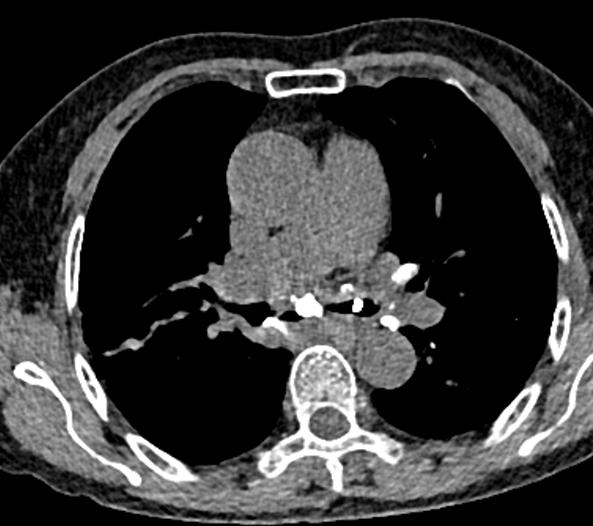

图10~图15 胸部CT示双肺多发钙化灶

问题出在哪儿?

右中间支气管的钙化病灶向外移动,钙化病灶的尖端刺激到支气管粘膜了(图16)。

图16 胸部CT

另外,这个患者的钙化灶非常危险,因为钙化灶的一端距离肺动脉才2毫米左右(图17),支气管镜下强行牵拉钙化病灶很可能会大出血危及生命。